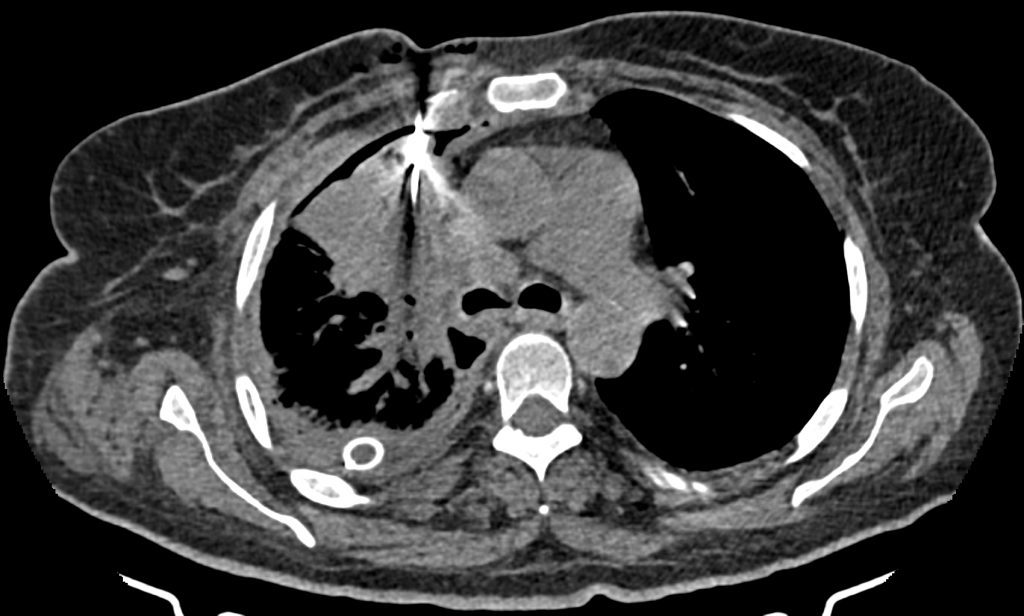

تحت هدايت سي تي اسکن سه نمونه CNB از توده سگمان آنتريور لوب فوقاني راست تهيه شد .

تصاوير پيوست قرارگيري سوزن در توده را نشان مي دهد .